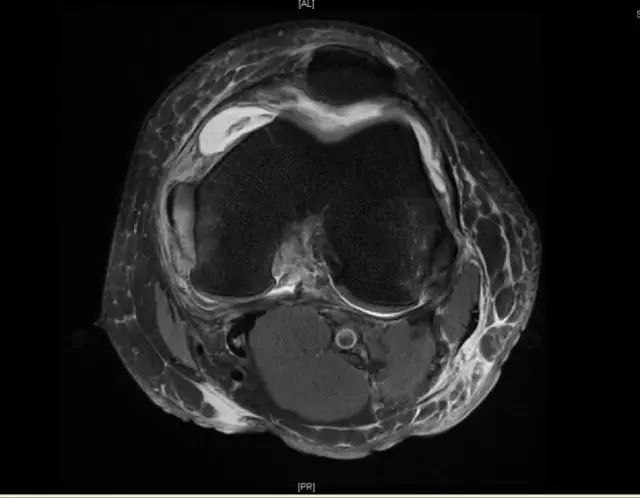

后交叉韧带断裂

这个病例韧带连续性中断松弛,尤其上止点的信号增高;从这个层面来看它的上止点形态不完整,部分信号增高;从这个层面可以看到,韧带的形态信号增粗,松弛,信号也是增高的,所以这个病例可以诊断为后交叉韧带断裂。